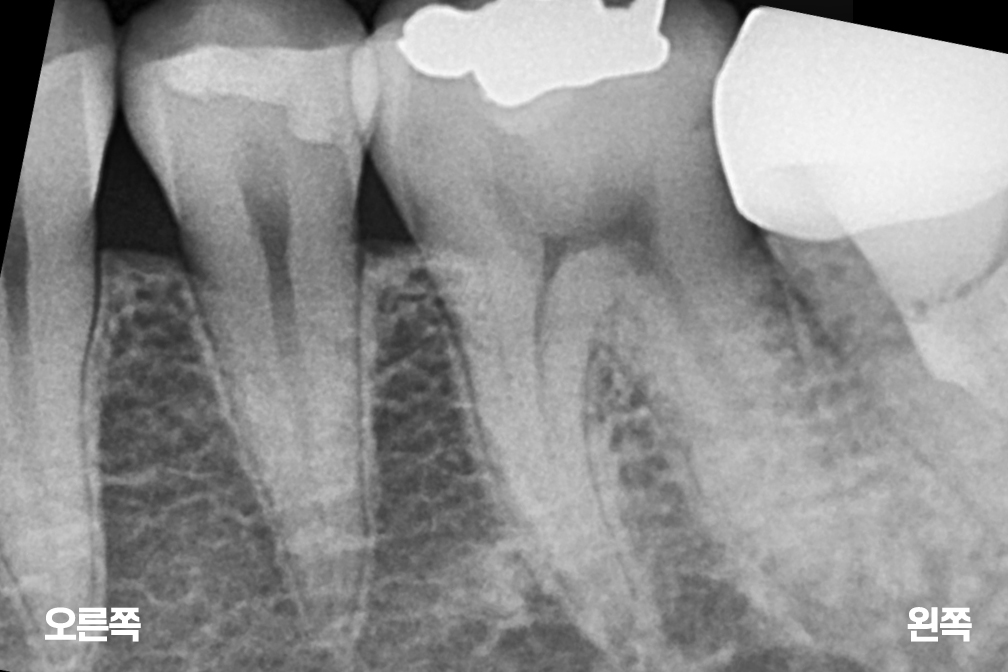

충치치료 왼쪽 아래 작은어금니(소구치) 충치치료

인레이

Before 2025년 6월 14일